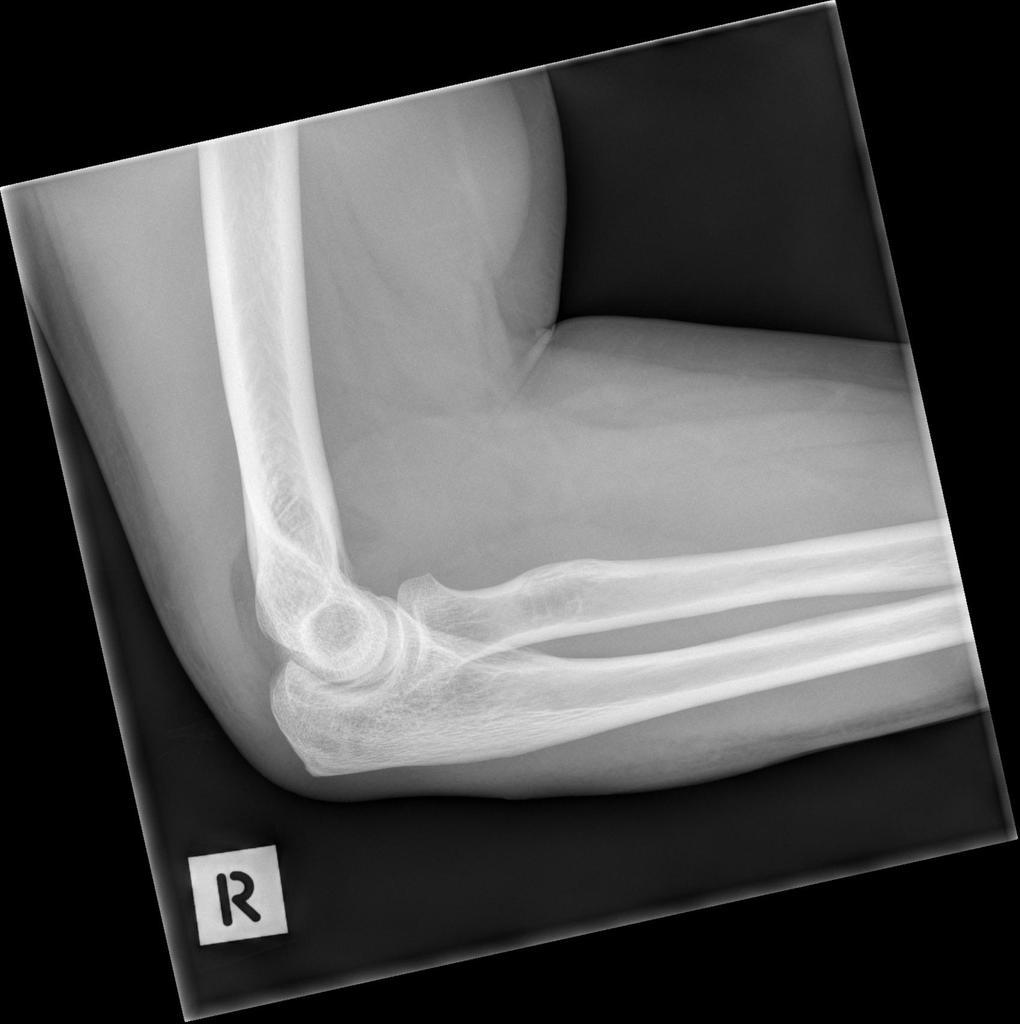

Sometimes no obvious fracture line for a supracondylar fracture can be identified. What should you look for instead?

What injury can be seen?

Supracondylar fracture